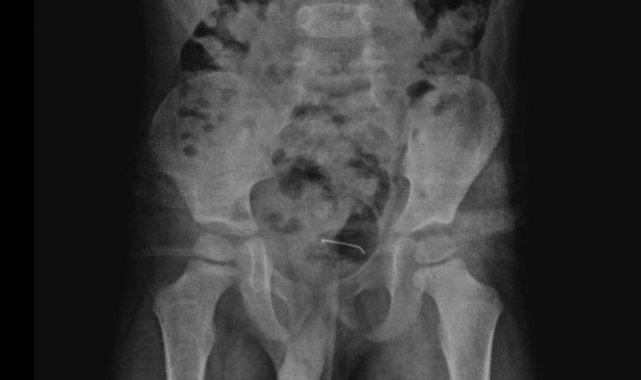

Daha önce farklı sağlık kuruluşlarına başvuran ancak kesin bir sonuç alamayan aile, çocuklarının karın ağrısı şikayetinin artması üzerine Tatvan Devlet Hastanesi Çocuk Cerrahisi Polikliniğine başvurdu. Yapılan röntgen incelemelerinde, mesane duvarında metal bir cisim olduğu tespit edildi. Uzun süre vücutta kalan 3 santimetrelik toplu iğnenin mesane duvarına yapıştığı belirlendi. Ailenin bilgilendirilmesinin ardından Tatvan Devlet Hastanesi Çocuk Cerrahi Uzmanı Op. Dr. Tahsin Onat Kamçı tarafından gerçekleştirilen operasyonla, toplu iğne başarılı bir şekilde çıkarıldı. Ameliyat sonrası birkaç gün gözlem altında tutulan çocuk, tekrar kontrole gelmek üzere taburcu edildi.

Hastanın kontrollerinde, yuttuğu cismin doğal yollarla vücuttan çıkmadığını tespit ettiklerini anlatan Kamçı, "Bunun üzerine ameliyat kararı aldık. Ameliyatta cismin mesane duvarına yapıştığını gördük. Cerrahi operasyonla 3 santimetre civarındaki toplu iğneyi çıkardık. Hastayı birkaç gün takipte tuttuk. Genel sağlık durumu iyi olan hastamızı taburcu ettik" diye konuştu.